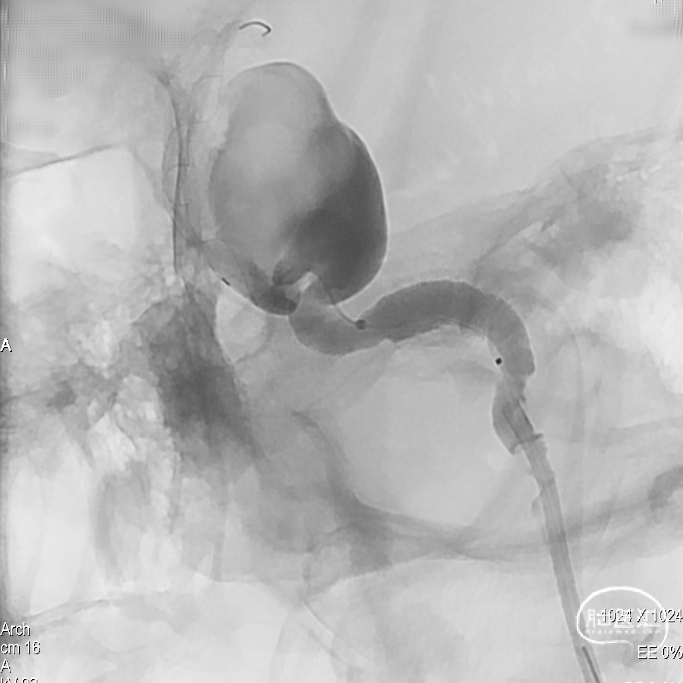

因载瘤动脉较为迂曲,为使支架头端锚定牢固, 4.5mmx45mm Tubridge血流导向密网支架前端1/3处采用稳定支撑系统逐步缓慢给张释放支架,使支架前端充分打开并与血管壁充分贴合。

当Tubridge血流导向密网支架释放到瘤颈弯段位置时,既要保障支架能充分打开、又要保障近端导管张力可控防止支架整体疝入动脉瘤囊内。因此采用节段性“推拉释放技术”既局部给张/松张,来回推挤技术释放支架,并通过持续造影观察支架打开、贴壁及血流转向效果等情况。

通过减影、显影所示,4.5mmx45mm Tubridge血流导向密网支架尾端长度充分且足够,为达到预设计的释放落脚点位置,支架尾端释放采用“推挤+减张瞬间释放技术”通过支架张力使尾端快速打开。

支架打开后即刻造影判断Tubridge血流导向密网支架已充分打开、贴合,同时可见瘤囊内造影剂滞留明显。

术后即刻造影显示,支架打开良好、贴壁充分,囊内有明显的滞留。